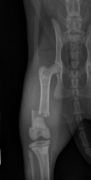

Dépistage officiel de la dysplasie de la hanche et du coude.